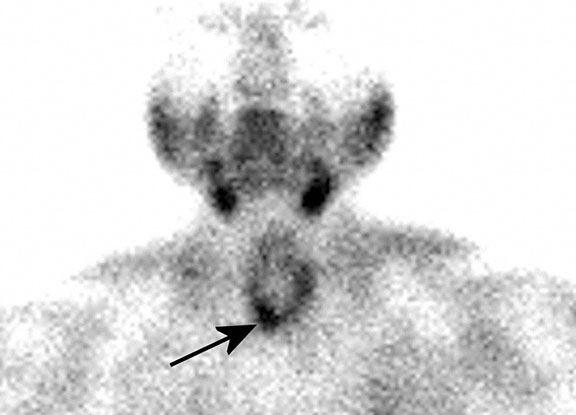

A 58-year-old woman comes to the physician because of a 6-month history of fatigue and muscle weakness. Physical examination shows no abnormalities. Serum studies show a calcium concentration of 11.8 mg/dL and intact parathyroid hormone concentration of 340 pg/mL. A nuclear parathyroid scan is shown; the arrow indicates a parathyroid adenoma in the region of the right lower pole of the thyroid gland. This adenoma is most likely located in which of the following labeled areas of the axial CT scan of the thyroid gland?